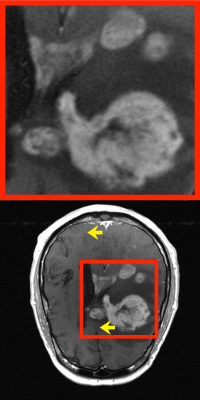

III-B Comparison study

This subsection validates the effectiveness of the proposed method and exhibits qualitative and quantitative comparison results to other reconstruction approaches such as inverse fast Fourier transform with zero filling (IFFT), compressed sensing with total variation penalty (CS), supervised learning using TransUNet [30] (SL) and k𝑘kitalic_k-space interpolation using neural representation [31] (INK).

In Fig. 2 and Table I, qualitative and quantitative comparisons are provided. The proposed method demonstrated the superior performance rather than IFFT, CS, and INK, while SL was comparable. As far as we have implemented, the neural representation in k𝑘kitalic_k-space appears to be less effective in terms of accuracy and stability. The intensity distribution over pixels in the image domain is strongly correlated even simply in a neighborhood region. However, it is complicatedly entangled in the k𝑘kitalic_k-space domain and fairly irrelevant in a local region, which might cause the increased training complexity, learning instability, performance degradation, and etc. Compared to SL, the proposed reconstruction appears to keep anatomical details. It may be a consequence of the high adaptiveness to the given data. We further elaborate and discuss this in Section IV.

Here, CS was implemented using the open-source package, named as SigPy [32]. We trained TransUNet using supervised learning with 532 paired data, whose input is an aliased MR image and label is the corresponding image reconstructed from full sampling. For INK, a multi-layer perceptron (21) was trained, which inputs a image coordinate and outputs a two dimensional vector representing a complex-valued k𝑘kitalic_k-space intensity. The network was trained by using observed k𝑘kitalic_k-space data and then used to interpolate unsampled values in k𝑘kitalic_k-space.

It should be mentioned that the comparison with SL is not fair. We note that the reconstruction approaches other than SL do not require any training data. The use of the larger number of training data can further improve the performance of SL and even can lead it to outperform the proposed method. Most importantly, however, our method is based only on single k𝑘kitalic_k-space data.